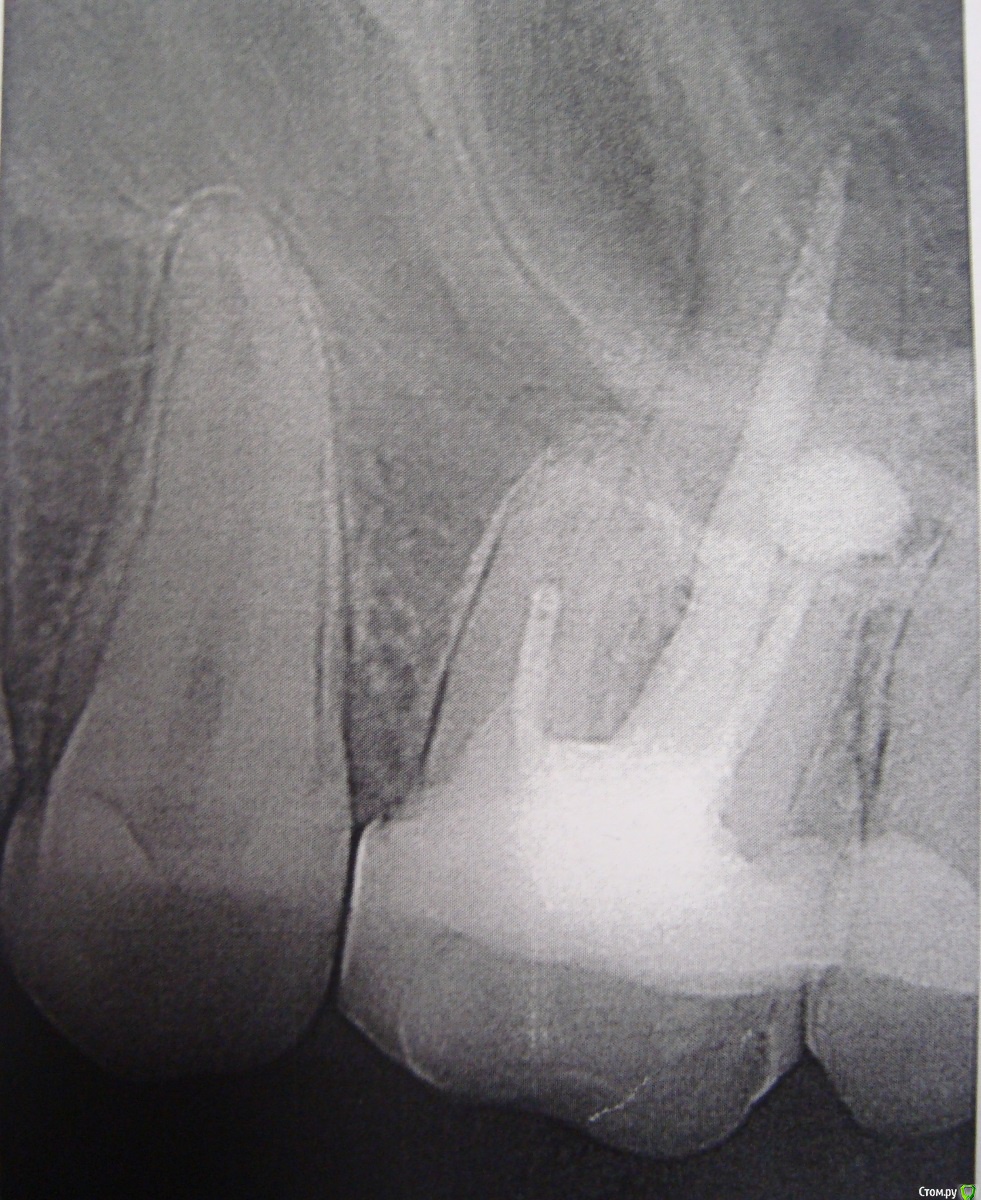

player543 Опубликовано 16 марта, 2015 Поделиться Опубликовано 16 марта, 2015 Здравствуйте.У меня иногда болит зуб при надавливании во время еды. Иногда несколько дней вообще не болит, в другой день при надавливании при каждом приеме пищи.Этот зуб был вылечен (пульпит) лет 7 назад, не помню делали ли рентген для проверки лечения.Эта нерегулярная боль при надавливании уже пару лет (и вроде бы не ухудшается). Помню что в течение года после лечения зуб болел при наклоне головы (но тоже не всегда). Прежде всего хочу разобраться в чем проблема зуба. Несколько стоматологов говорили что все из-за того, что пломбировочный материал попал в гайморову пазуху, предлагали идти к ЧЛХ и как-то там это "вычищать". Последний врач сказал что там канал до конца не заполнен и там живет инфекция. Почему-то сказал что нужно удалять зуб, а я не спросил почему.Ваше мнение в чем проблема зуба? И второе - как его лечить? Просто перелечивание каналов? Можно ли перелечить только 1 канал или только все сразу? Этот зуб был восстановлен более чем на 1/2 если это важно. Ссылка на комментарий

Гарриевич Опубликовано 16 марта, 2015 Поделиться Опубликовано 16 марта, 2015 Лечить можно двумя путями1- перелечивать все корневые каналы2- только каналы передне-щечного корня Ссылка на комментарий

red_butler Опубликовано 17 марта, 2015 Поделиться Опубликовано 17 марта, 2015 Для начала хорошо бы сделать Кт, и посмотреть верхнечелюстной синус. Далее повторное лечение с последующим протезированием. Точный объем лечения будет понятен в процессе.Показаний к удалению не увидел Ссылка на комментарий